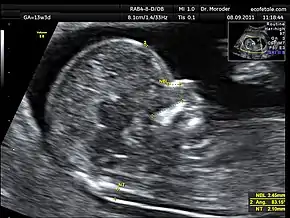

Enlarged NT and absent nasal bone in a fetus at 11 weeks with Down syndrome

Overall, the most common chromosomal disorder is Down syndrome (trisomy 21). The likelihood rises with maternal age from 1 in 1400 pregnancies below age 25, to 1 in 350 at age 35, to 1 in 200 at age 40.[4]